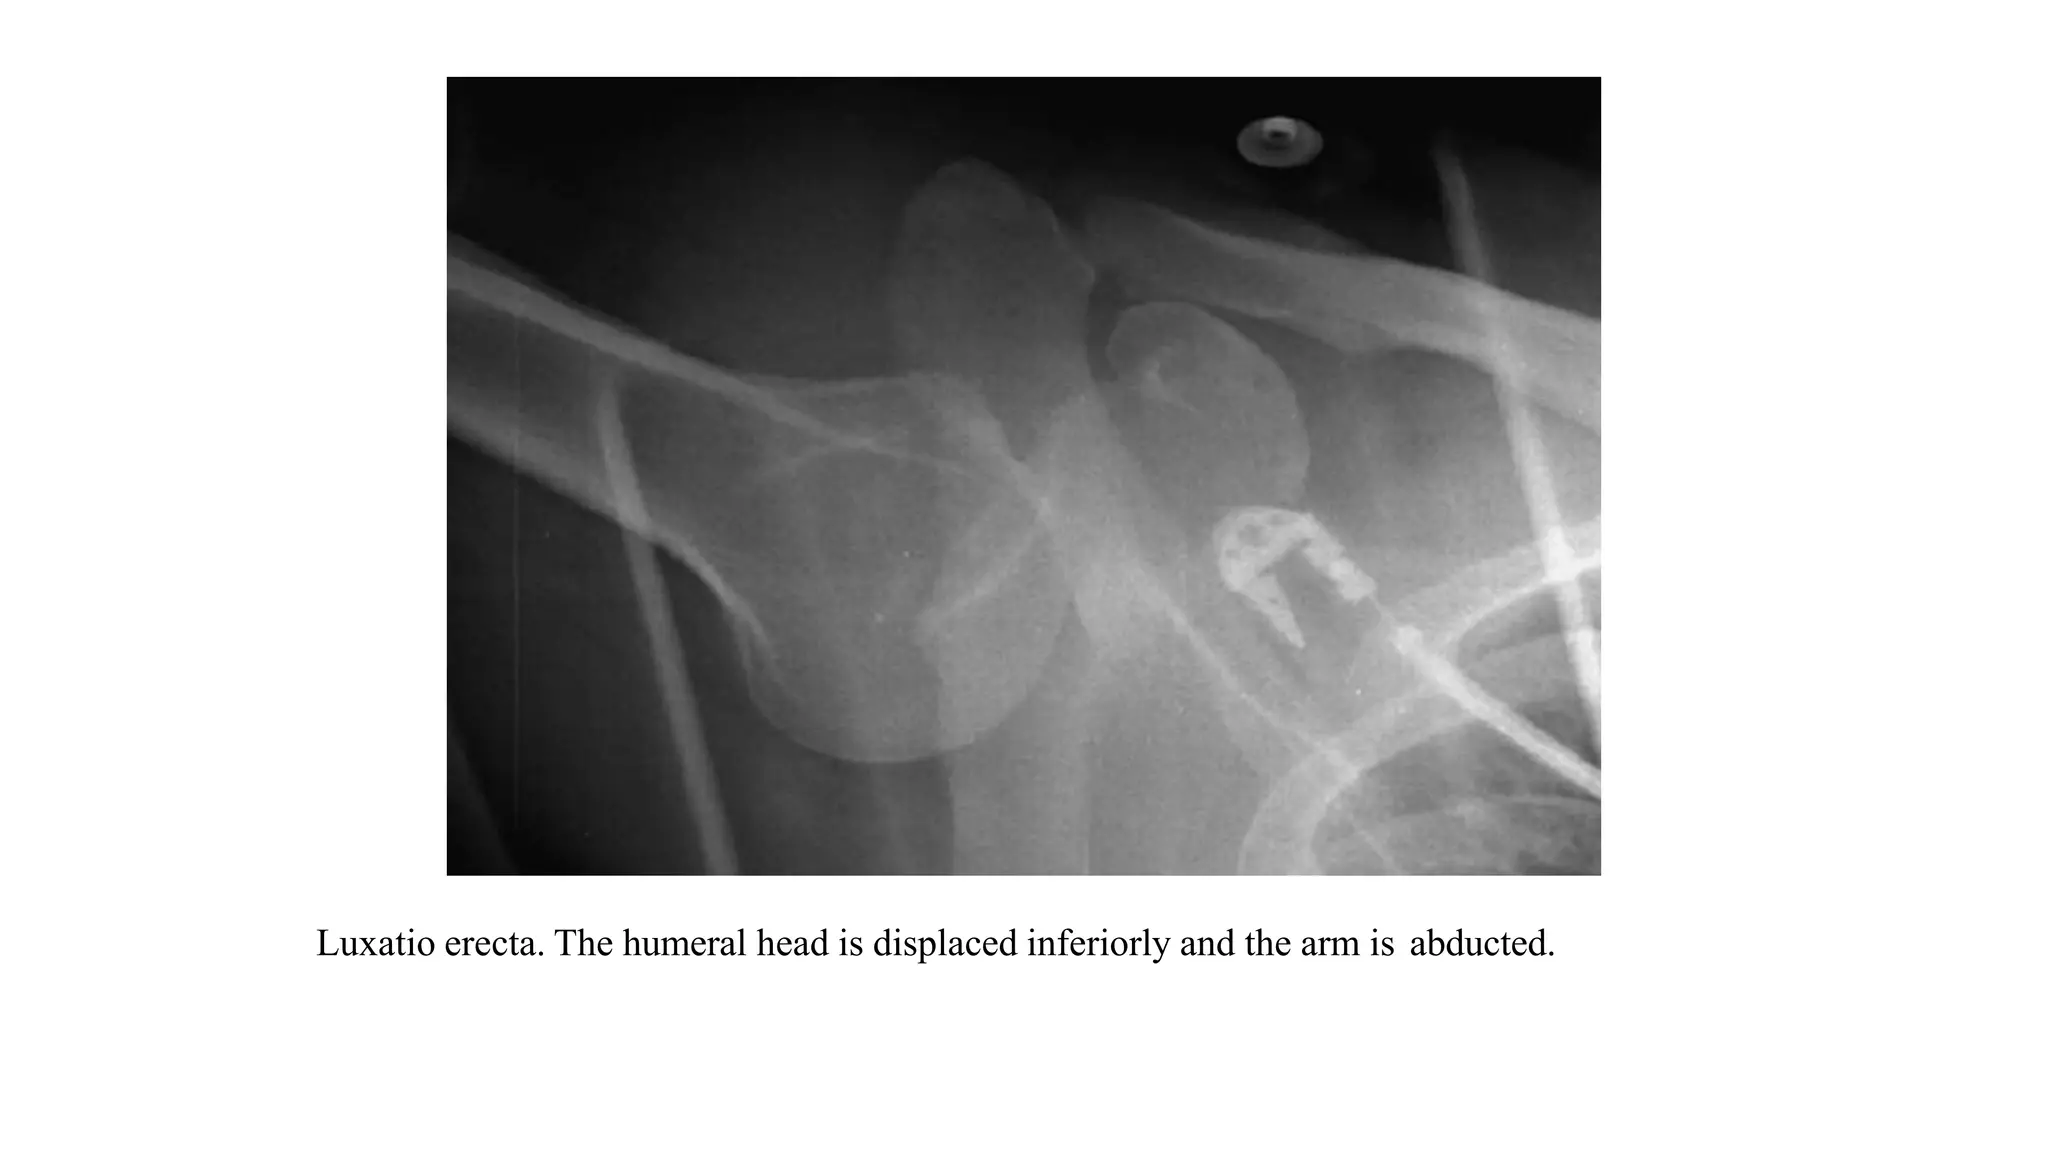

LUXATIO ERECTA

• Luxatio erecta is also called inferior or subglenoid dislocation.

• In this injury, the arm is raised, abducted and cannot be lowered.

• Causes of luxatio erecta include hyperabduction and extension during a fall and

attempting overhead shots in racket sports.

• Typical radiographic features of luxatio erecta include humeral head dislocation

inferior to the glenoid with the humerus locked in abduction.

• Associated injuries:

• 80% of the cases have associated greater tuberosity fracture or rotator cuff tear.

• 60% of the cases have some degree of neurological impairment, most frequently to the

axillary nerve.

• 3.3% of the cases have significant vascular compromise.

Luxatio erecta. The humeral head is displaced inferiorly and the arm is abducted.

Luxatio erecta. AP radiograph of shoulder demonstrates humeral head (arrow) to be displaced

directly inferiorly relative to glenoid fossa and arm is fixed in fully abducted position.